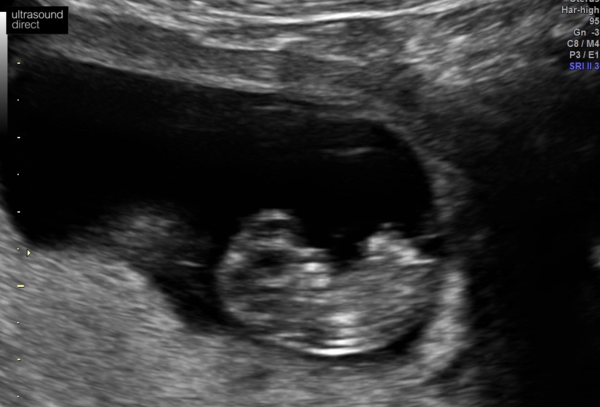

Ooh so many messages to catch up on!! So I bit the bullet and booked for a private scan and was able to get an appointment last night. I haven’t had any worrying symptoms but it’s my first and I’ve been a concerned in general about how things are progressing.

Anyway, apparently baby looks fine and has a strong heartbeat. She dated me at 9+6 but according to my LMP I was 9+3.... is it normal that they say your future along than you think? She did say not to take this as gospel and wait for dating scan.

Was just a relief to know baby is definitely in there and doing ok - like lots of people on here my morning sickness has been fairly mild and some days non existent so have faith!!

sazzlerazzle · 03/10/2019 19:14

Here’s the little bean

@sazzlerazzle ahhhh beautiful pictures, so pleased all is well! Xx

Ahh congratulations @sazzlerazzle what a lovely picture xx

Congrats @sazzlerazzle! What was the baby measuring at? Yes can be put forward or back... but then baby can catch up/slow down with LMP I think!